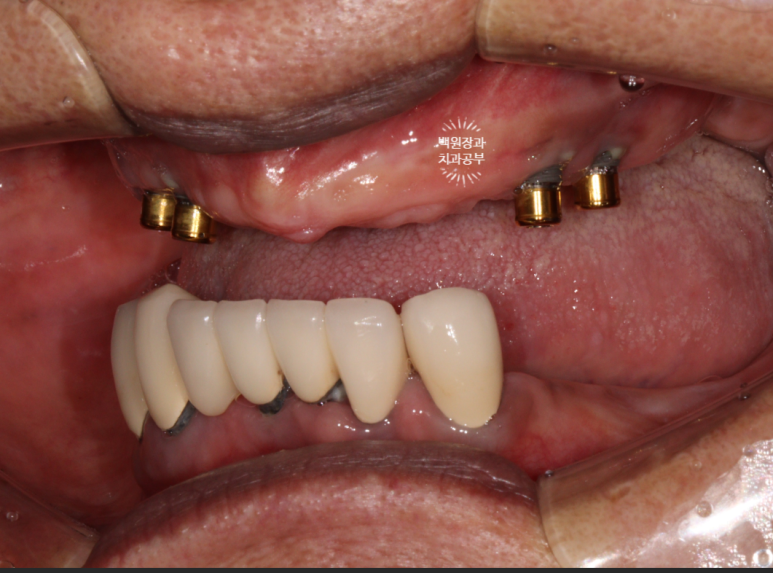

70대 중반 남자 환자분이셨습니다.

위턱에 네개의 임플란트를 이용한 임플란트틀니를 5년 동안 사용하고 계셨는데, 계속 고름이 나오신다는거에요...

노란 점선이 보이시나요? 잇몸뼈의 높이입니다.

상당한 양의 임플란트 주변 뼈가 녹아서 없어져 버린것을 보실 수 있어요.

환자분은 임플란트를 엄청 빼고싶어 하셨습니다.

저희 치과 잘 찾아오셨습니다....!

금색의 locator가 장착된 임플란트의 주변에 고름이 맺혀있는게 보이시나요..?

네개의 임플란트 모두 상당한 임플란트주위염에 시달리고 있는 것을 볼 수 있었습니다.